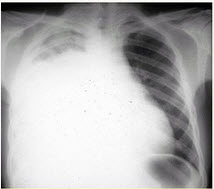

患者男,73岁。进行性呼吸困难半年,加重2个月。否认吸烟史、粉尘接触史。查体:发绀,杵状指,双肺底闻爆裂音。血常规正常,ERS16mm/h。胸部CT如图所示: